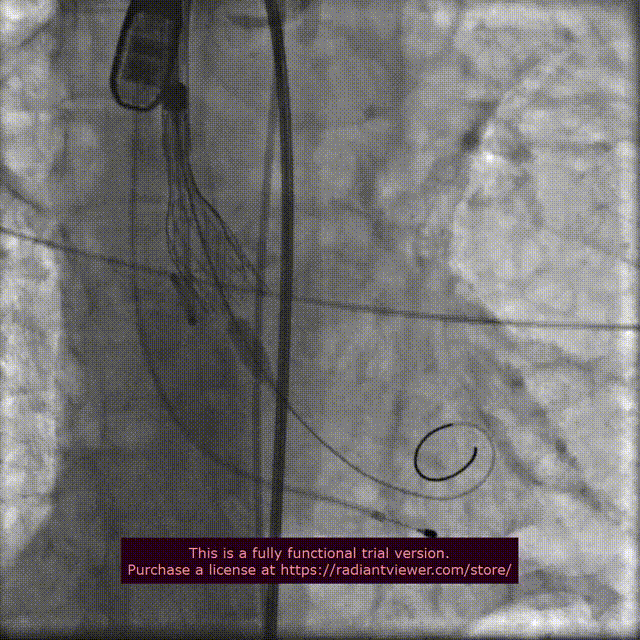

行主动脉根部造影后,直头导丝成功跨瓣,选择左冠切线位进行球囊预扩;TaurusElite AV23瓣膜送至主动脉弓,主动脉根部再次造影,并取零位释放位置。

球 囊 预 扩

瓣膜精准定位

术中结合DSA、超声影像,多角度观察显示:瓣周漏及反流显著,遂决定球囊后扩,行18mm TaurusAtlas球囊进行后扩。

主动脉根部造影,瓣周漏显著

18mm球囊扩张,无冠窦形态欠佳

18mm TaurusAtlas球囊后扩张,超声显示瓣周漏及反流改善不明显,在瓣膜可能移位的风险下决定行20mm TaurusAtlas球囊后扩,结果效果理想,血流动力学显著改善。

20mm球囊扩张

主动脉根部造影,血流动力学稳定,微量反流